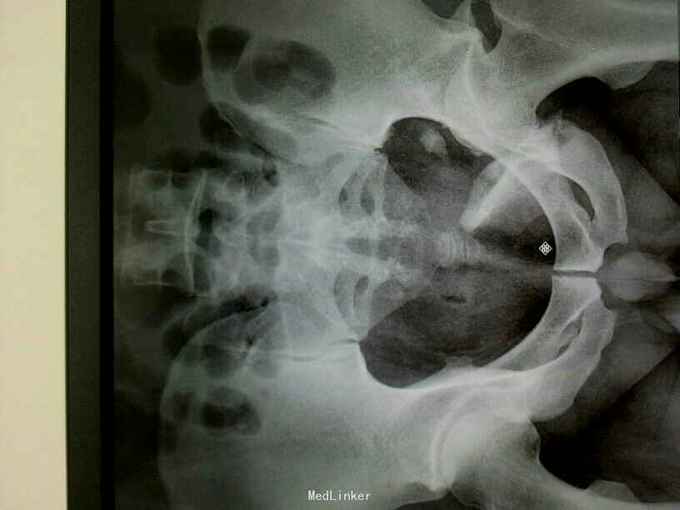

专科情况:患者平车推入病房,左股骨髁上骨牵引中,左髋部压痛、叩击痛(+),左髋关节主动活动受限,被动活动可引起明显疼痛,骨盆挤压、分离试验(-),脊柱、余肢体无畸形及压痛、叩击痛,关节无红肿、活动自如。双侧膝、跟腱反射正常,双侧Babinski征阴性。 辅助检查:骨盆三维重建CT示:左侧髋臼及耻骨下支骨质不连续,见多发不规则形骨折线,骨折断端错位成角,可见多发游离骨片,股骨头向后移位,其周软组织肿胀。